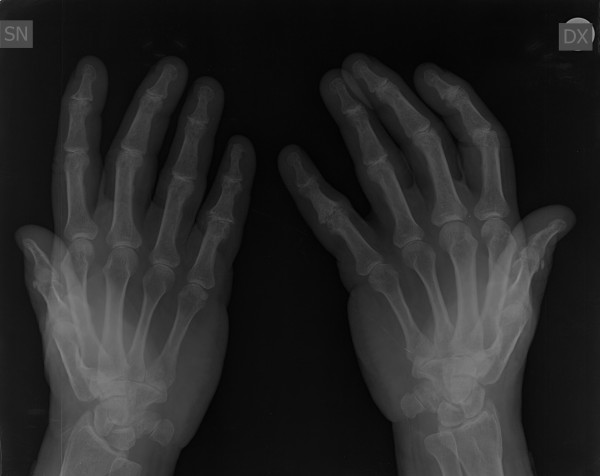

Mi piacerebbe avere un ulteriore parere sulla radiografia alle mani che allego anche per una eventuale cura da seguire. Grazie!!

0006B312.jpg

[ 24.9 KiB | Osservato 1617 volte ]

0006B311.jpg

[ 27.61 KiB | Osservato 1617 volte ]

0006B310.jpg

[ 32.51 KiB | Osservato 1617 volte ]

Non ha senso un parere del reumatologo quando esiste un referto del radiologo. Il problema potrebbe nascere se il quadro clinico e/o di laboratorio fossero in disaccordo con i dati radiologici. E' solo dal confronto dei 3 elementi (clinico in primis, poi radiologico e di laboratorio) che si può azzardare una diagnosi e quindi impostare un trattamento. Le macchine finora non sostituiscono del tutto il medico.